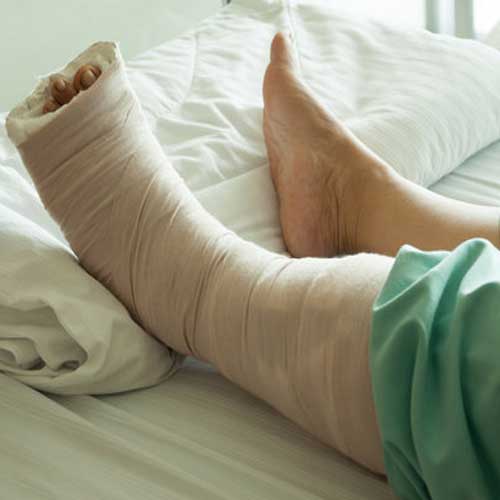

Fracture treatment and Surgery, including management of Non-union, Deformity Correction and Bone Infection Treatment